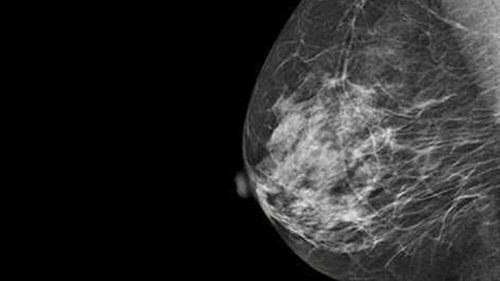

La mamografía es una potente herramienta que ayuda a detectar el cáncer de mama. (Foto: Universidad de Belgrano / Argentina Investiga)